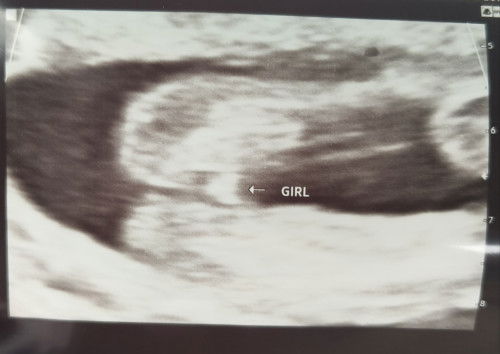

Confirm ya baby girls?

18minggu 3hari.. excited nak tau jantina walaupun dh ada ank sepasang.. confirm kan girl mcm ni? Sebab xnmpk ciri2 boys tp itulah selalu risau baby girl selalu scam.. hihihi

ni awk scan biasa atau details scan..NK tepat bt details scan .

Boleh repeat scan at 20 weeks - 24 weeks. No worries okay